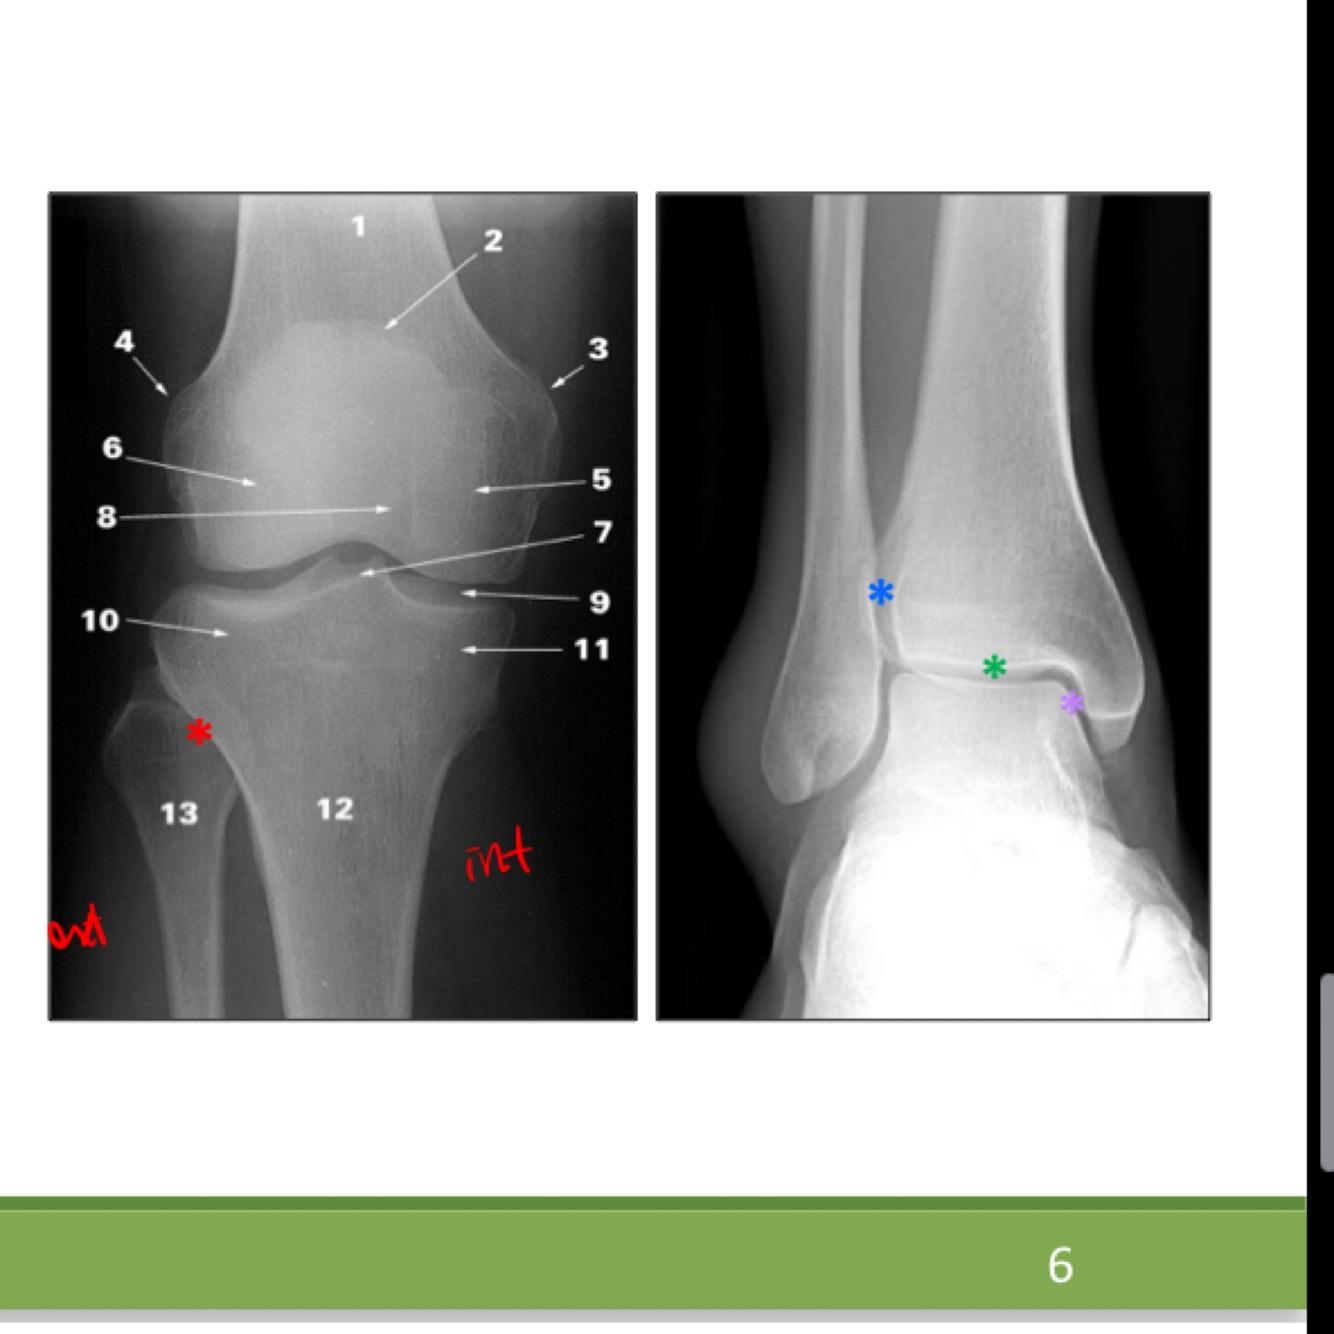

Nomme les chiffres sur l epiphyse proximale du tibia svp bibiboubobibou

les surfaces articulaires des condyles médial (1) et latéral (2) En vert: l'éminence intercondylaire. -Aire intercondylaires antérieure (7) et postérieure (8) -tubercules intercondylaires médial (5) et latéral (6) (Le médial se situe au bord latéral de la surface articulaire du condyle médial et le latéral se situe au bord médial de la surface articulaire du condyle latéral) ouin ca gosse

31

L aire intercondylaire antérieure de lepiphyse proximale du tibia (7) donne l’insertion de 2 structures…lesquelles

-Les cornes antérieures des ménisques médial et latéral du genou - ligament croisé antérieur

L aire intercondylaire postérieure (8) de l epiphyse proximale du tibia donne l insertion de deux structures

-cornes postérieures des ménisques médial et latéral du genou -ligament croisé postérieur

Quesqui s insère sur la tubérosité tibiale?

La surface articulaire fibulaire se situe sur la face ___________ du condyle _________ du tibia

La face posterolaterale du condyle lateral

Quesqui s'insère sur le relief en vert sur l'image

Il s’y insère le tractus iliotibial et quelques fibres du muscle tibial antérieur (Le relief en vert est est le tubercule du tractus iliotibial)